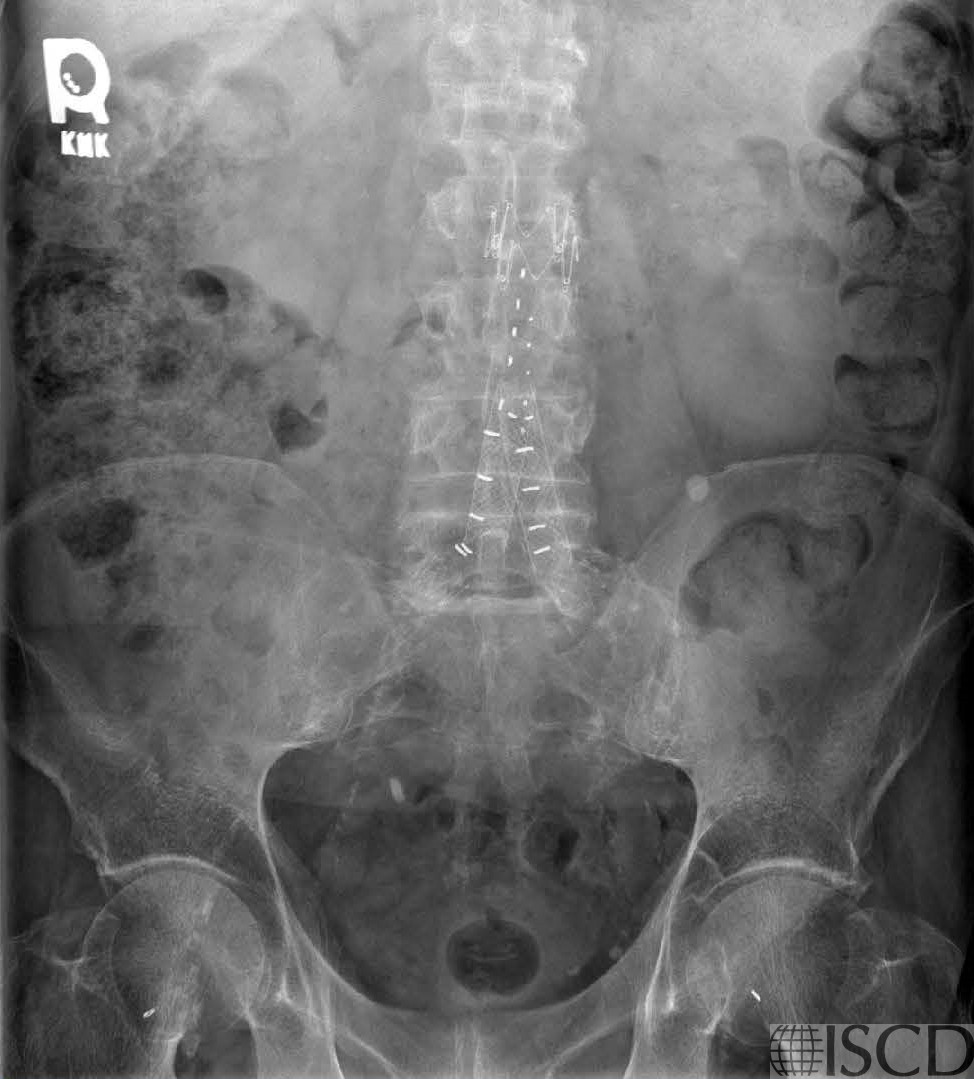

This is the accompanying radiograph which shows the endograft and clips.

There is an endograft and clips overlying the lumbar spine DXA image. Since the endograft overlies bone, the lumbar spine DXA will not be useful for diagnosis or follow-up.